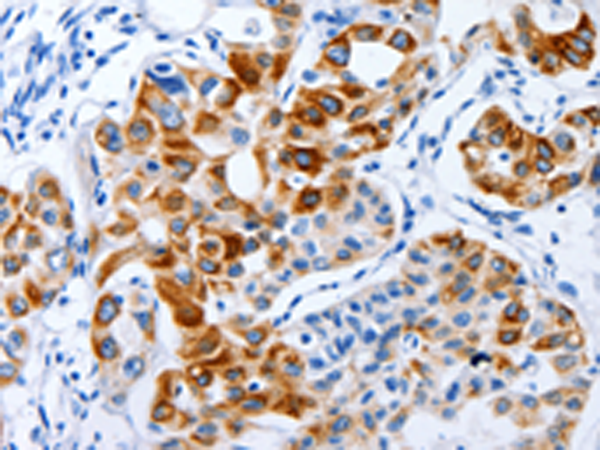

分类: 科研抗体货号: P11004别名: LIG1; LIG-1应用: WB,IHC反应种属: Human, Mouse